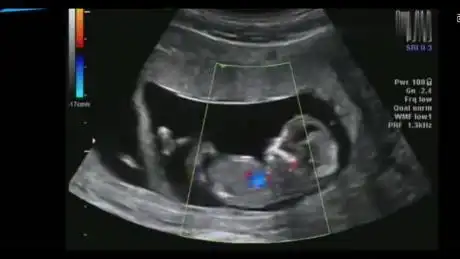

怀孕12周,b超影像记录下胎动真相的珍贵时刻,好神奇的一幕!